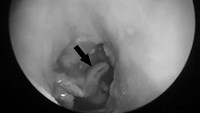

Pemeriksaan klinis menunjukkan lesi erosif atau kerusakan di belakang telinga kanan dengan bekas luka operasi sebelumnya. Setelah mengamati lebih dekat, dokter mengamati beberapa benda asing putih yang mudah bergerak di telinganya dan diambil untuk diperiksa lebih lanjut. Pemeriksaan otoskopi menunjukkan pembengkakan liang telinga luar dan keberadaan larva lalat (miasis) atau belatung. Kasus ini diterbitkan di jurnal Cureus dengan judul 'Aural Myiasis: A Case Report on a Rare Entity' pada 2020. (Foto: Journal Cureus)

Pemeriksaan klinis menunjukkan lesi erosif atau kerusakan di belakang telinga kanan dengan bekas luka operasi sebelumnya. Setelah mengamati lebih dekat, dokter mengamati beberapa benda asing putih yang mudah bergerak di telinganya dan diambil untuk diperiksa lebih lanjut. Pemeriksaan otoskopi menunjukkan pembengkakan liang telinga luar dan keberadaan larva lalat (miasis) atau belatung. Kasus ini diterbitkan di jurnal Cureus dengan judul Aural Myiasis: A Case Report on a Rare Entity pada 2020. (Foto: Journal Cureus)